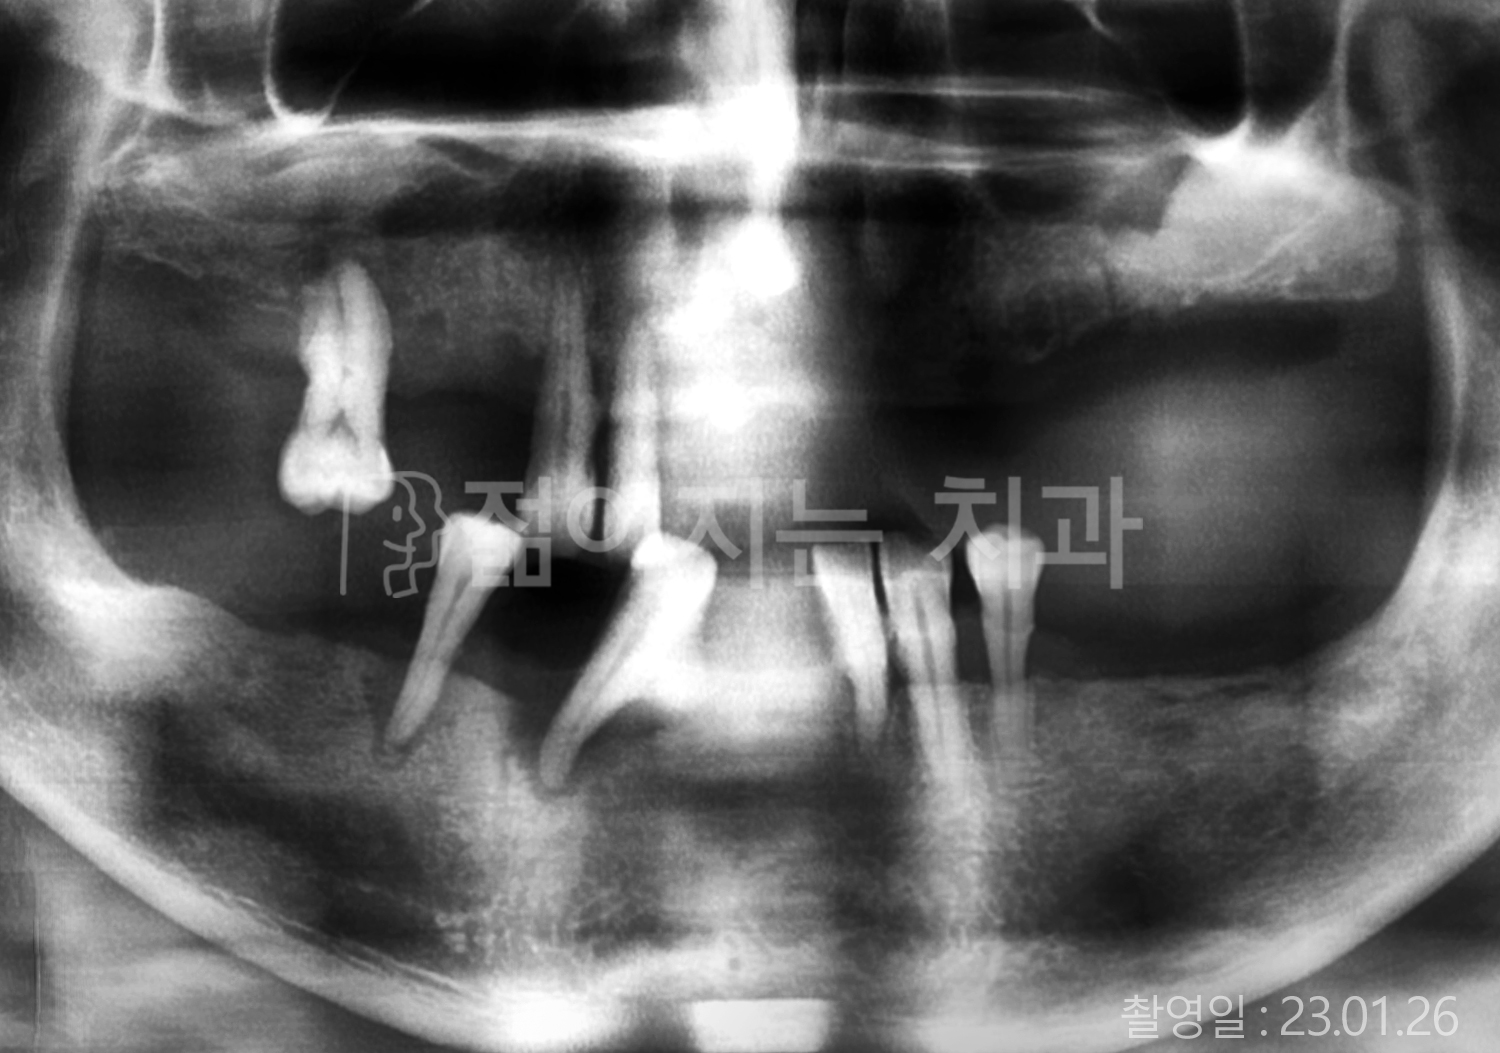

• 70대 고혈압, 고지혈증 전체치아 10개 이상 임플란트

• 60대 당뇨, 간염 전체치아 10개 이상 임플란트

• 80대 골다골증 전체치아 6개 이상 임플란트

• 70대 고혈압, 당뇨 전체치아 10개 이상 임플란트

• 60대 간 질환 전체치아 10개 이상 임플란트

• 60대 전체치아 10개 이상 임플란트

• 70대 전체치아 10개 이상 임플란트

• 50대 전체치아 10개 이상 임플란트

• 60대 고혈압, 고지혈증 전체치아 10개 이상 임플란트

• 40대 고지혈증, 뇌혈관 질환 전체치아 10개 이상 임플란트